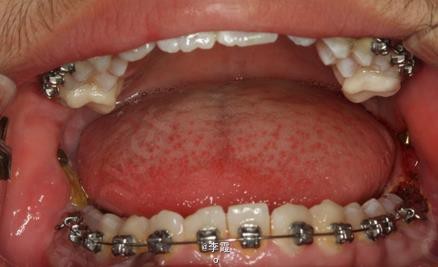

患者、马xx、15岁,主诉:牙齿不齐,要求正畸治疗。 转诊外科行下颌升支处种植体支抗直立下颌磨牙。通过患者的术前影像资料,47牙冠远中有部分骨质覆盖牙冠,采取翻瓣导萌直立磨牙。37采取电刀环切导萌直立磨牙。